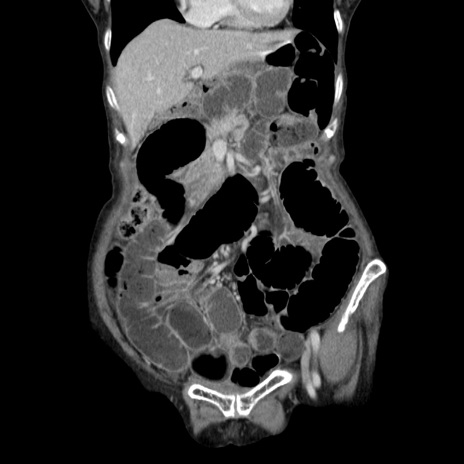

症例25(冠状断像)

【症例】80歳代女性

【主訴】胸のつかえ感

【現病歴】約9時間前に食後から胸のつかえた感じあり、嘔吐あり、来院。

【既往歴】胃癌(全摘)、胆摘、虫垂炎

【身体所見】心窩部に圧痛あり、反跳痛なし。

【データ】WBC 5700、CRP 0.05